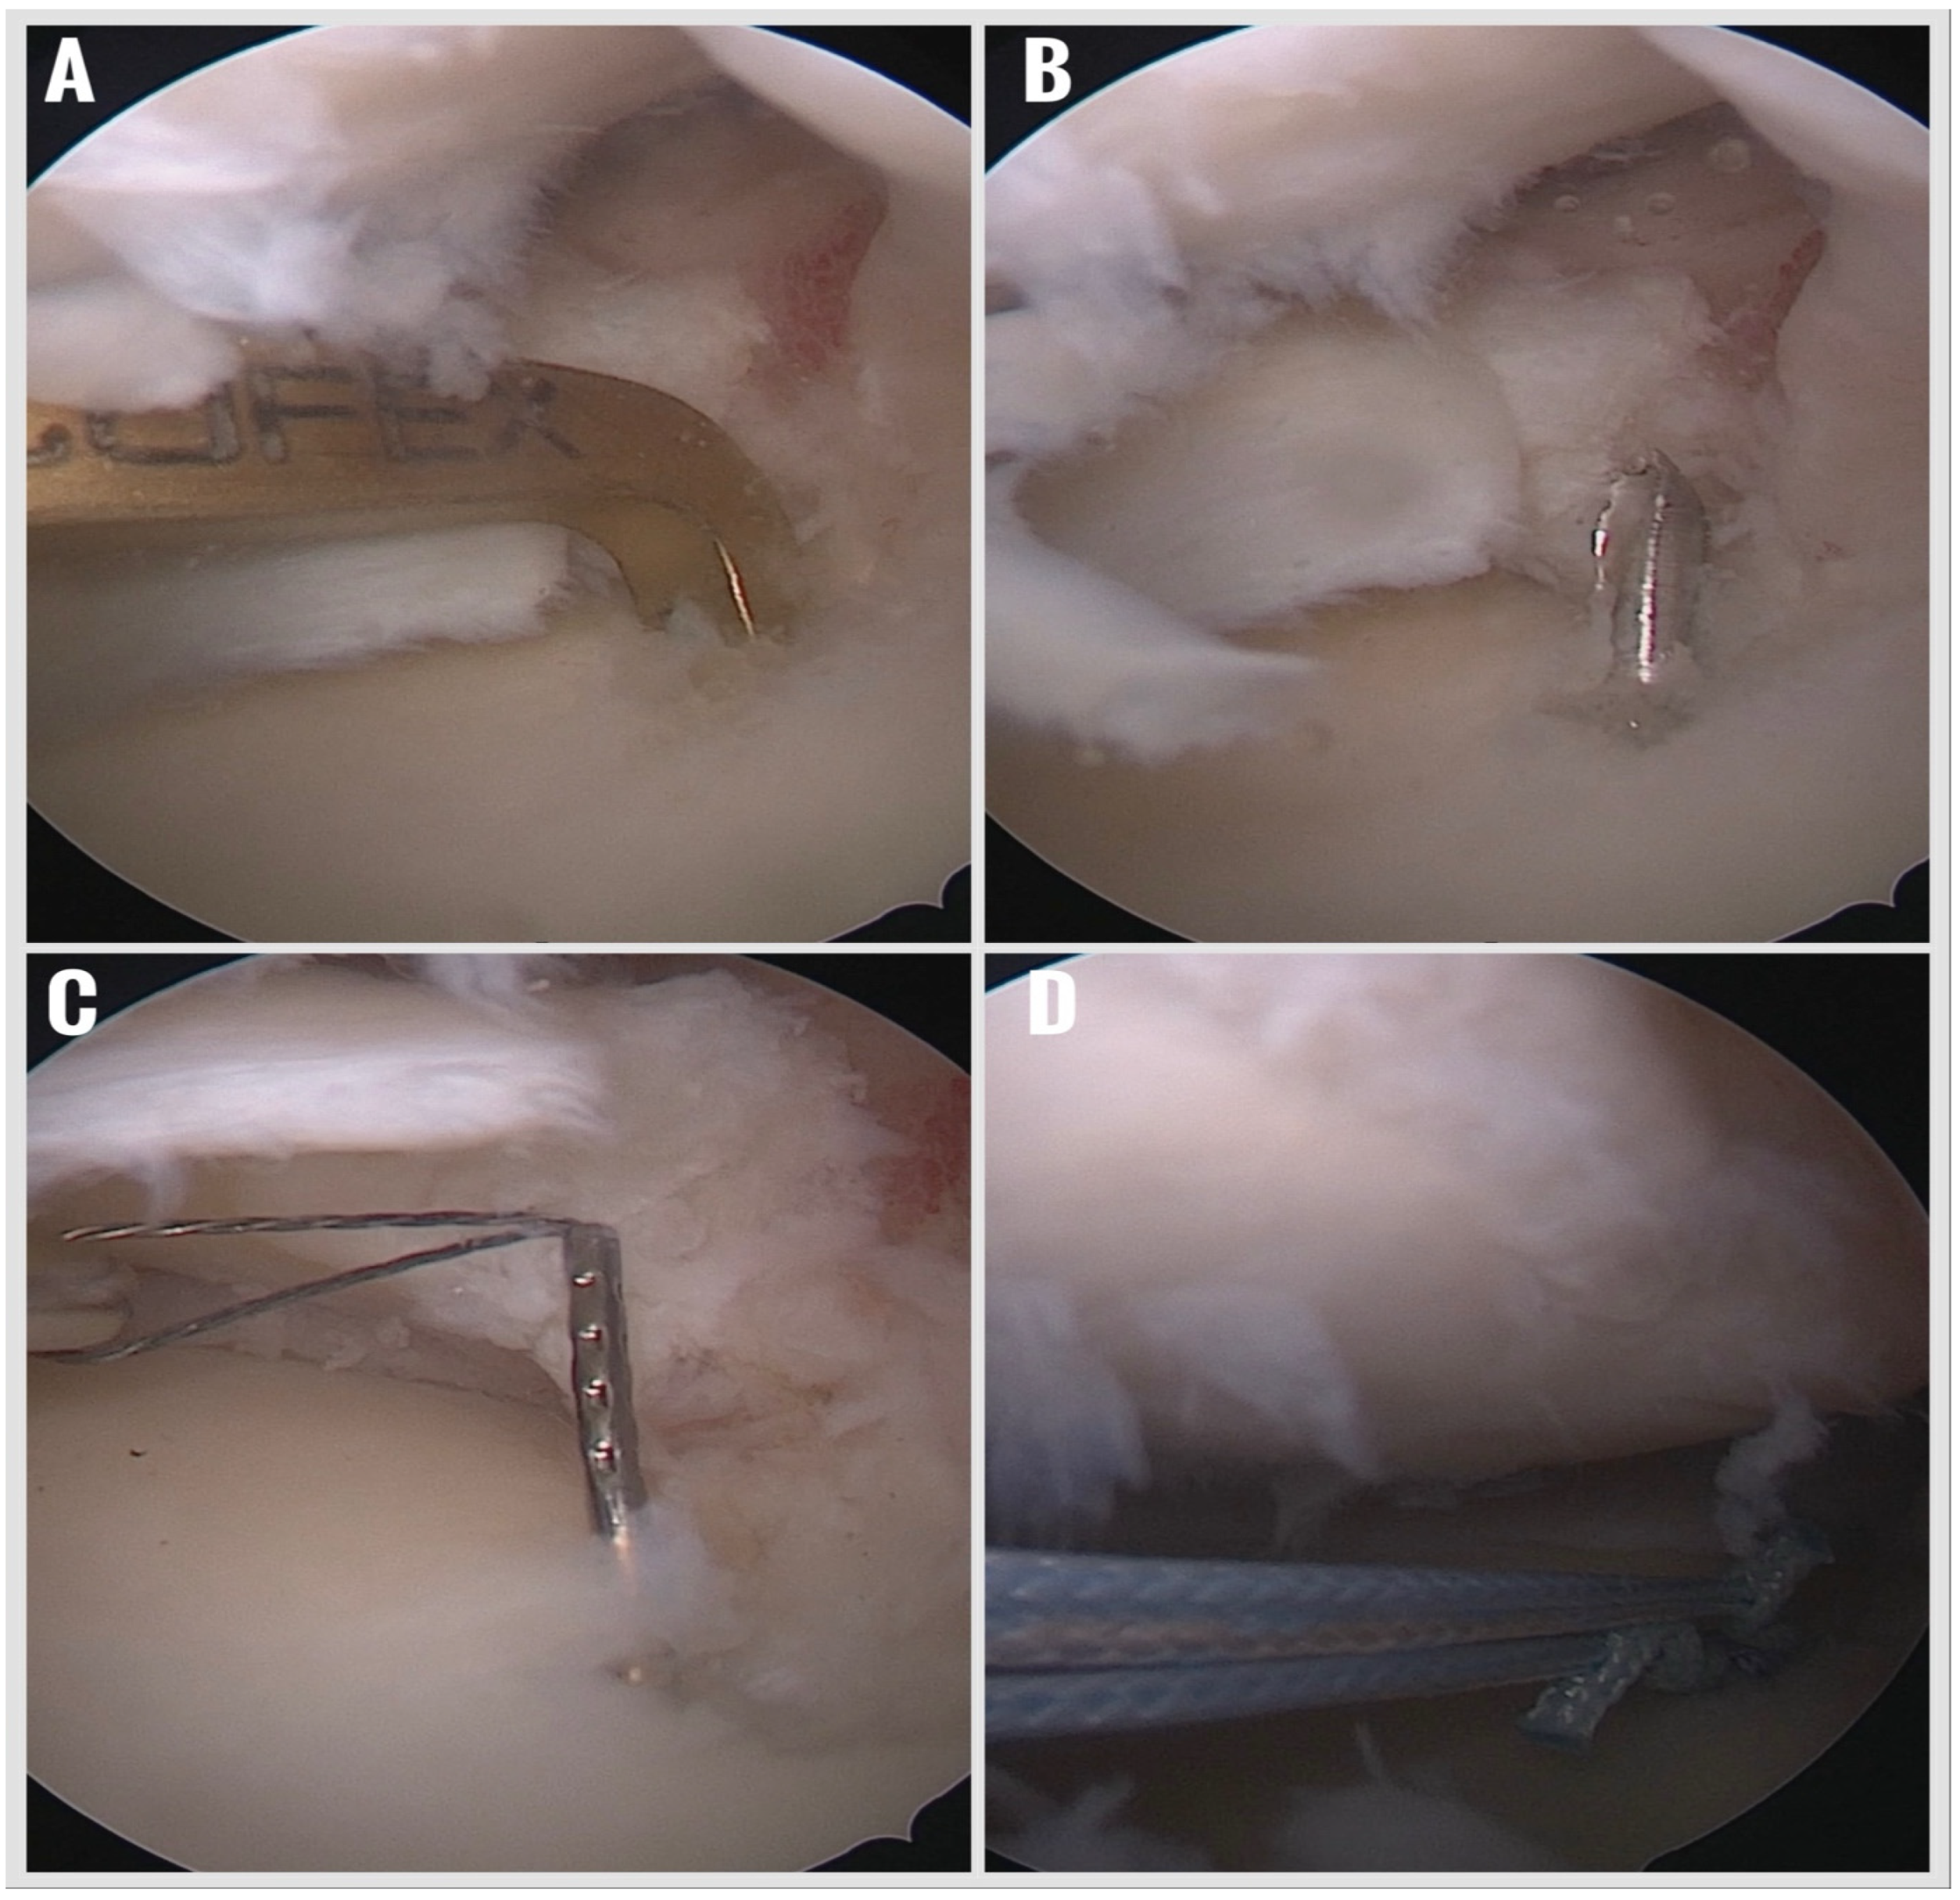

Figure 2. Preparation of torn meniscus and tibial insertion area. (A) Detection of a meniscus root tear with an arthroscopic probe. (B) Debridement and revitalization of the torn meniscus edges using a shaver. (C) Debridement of the meniscus tibial footprint with a curette. (D) Prepared state of the footprint and torn menisci. Following surgery, a standardized rehabilitation protocol was initiated.

Preparation of the Footprint and Meniscal Tissue:

The torn meniscal root was gently debrided using a motorized shaver to remove frayed tissue and expose healthy edges. The original tibial insertion site was prepared with a curette to remove the fibrocartilaginous layer and expose a bleeding subchondral bone bed, enhancing biological healing potential (Figure 2).